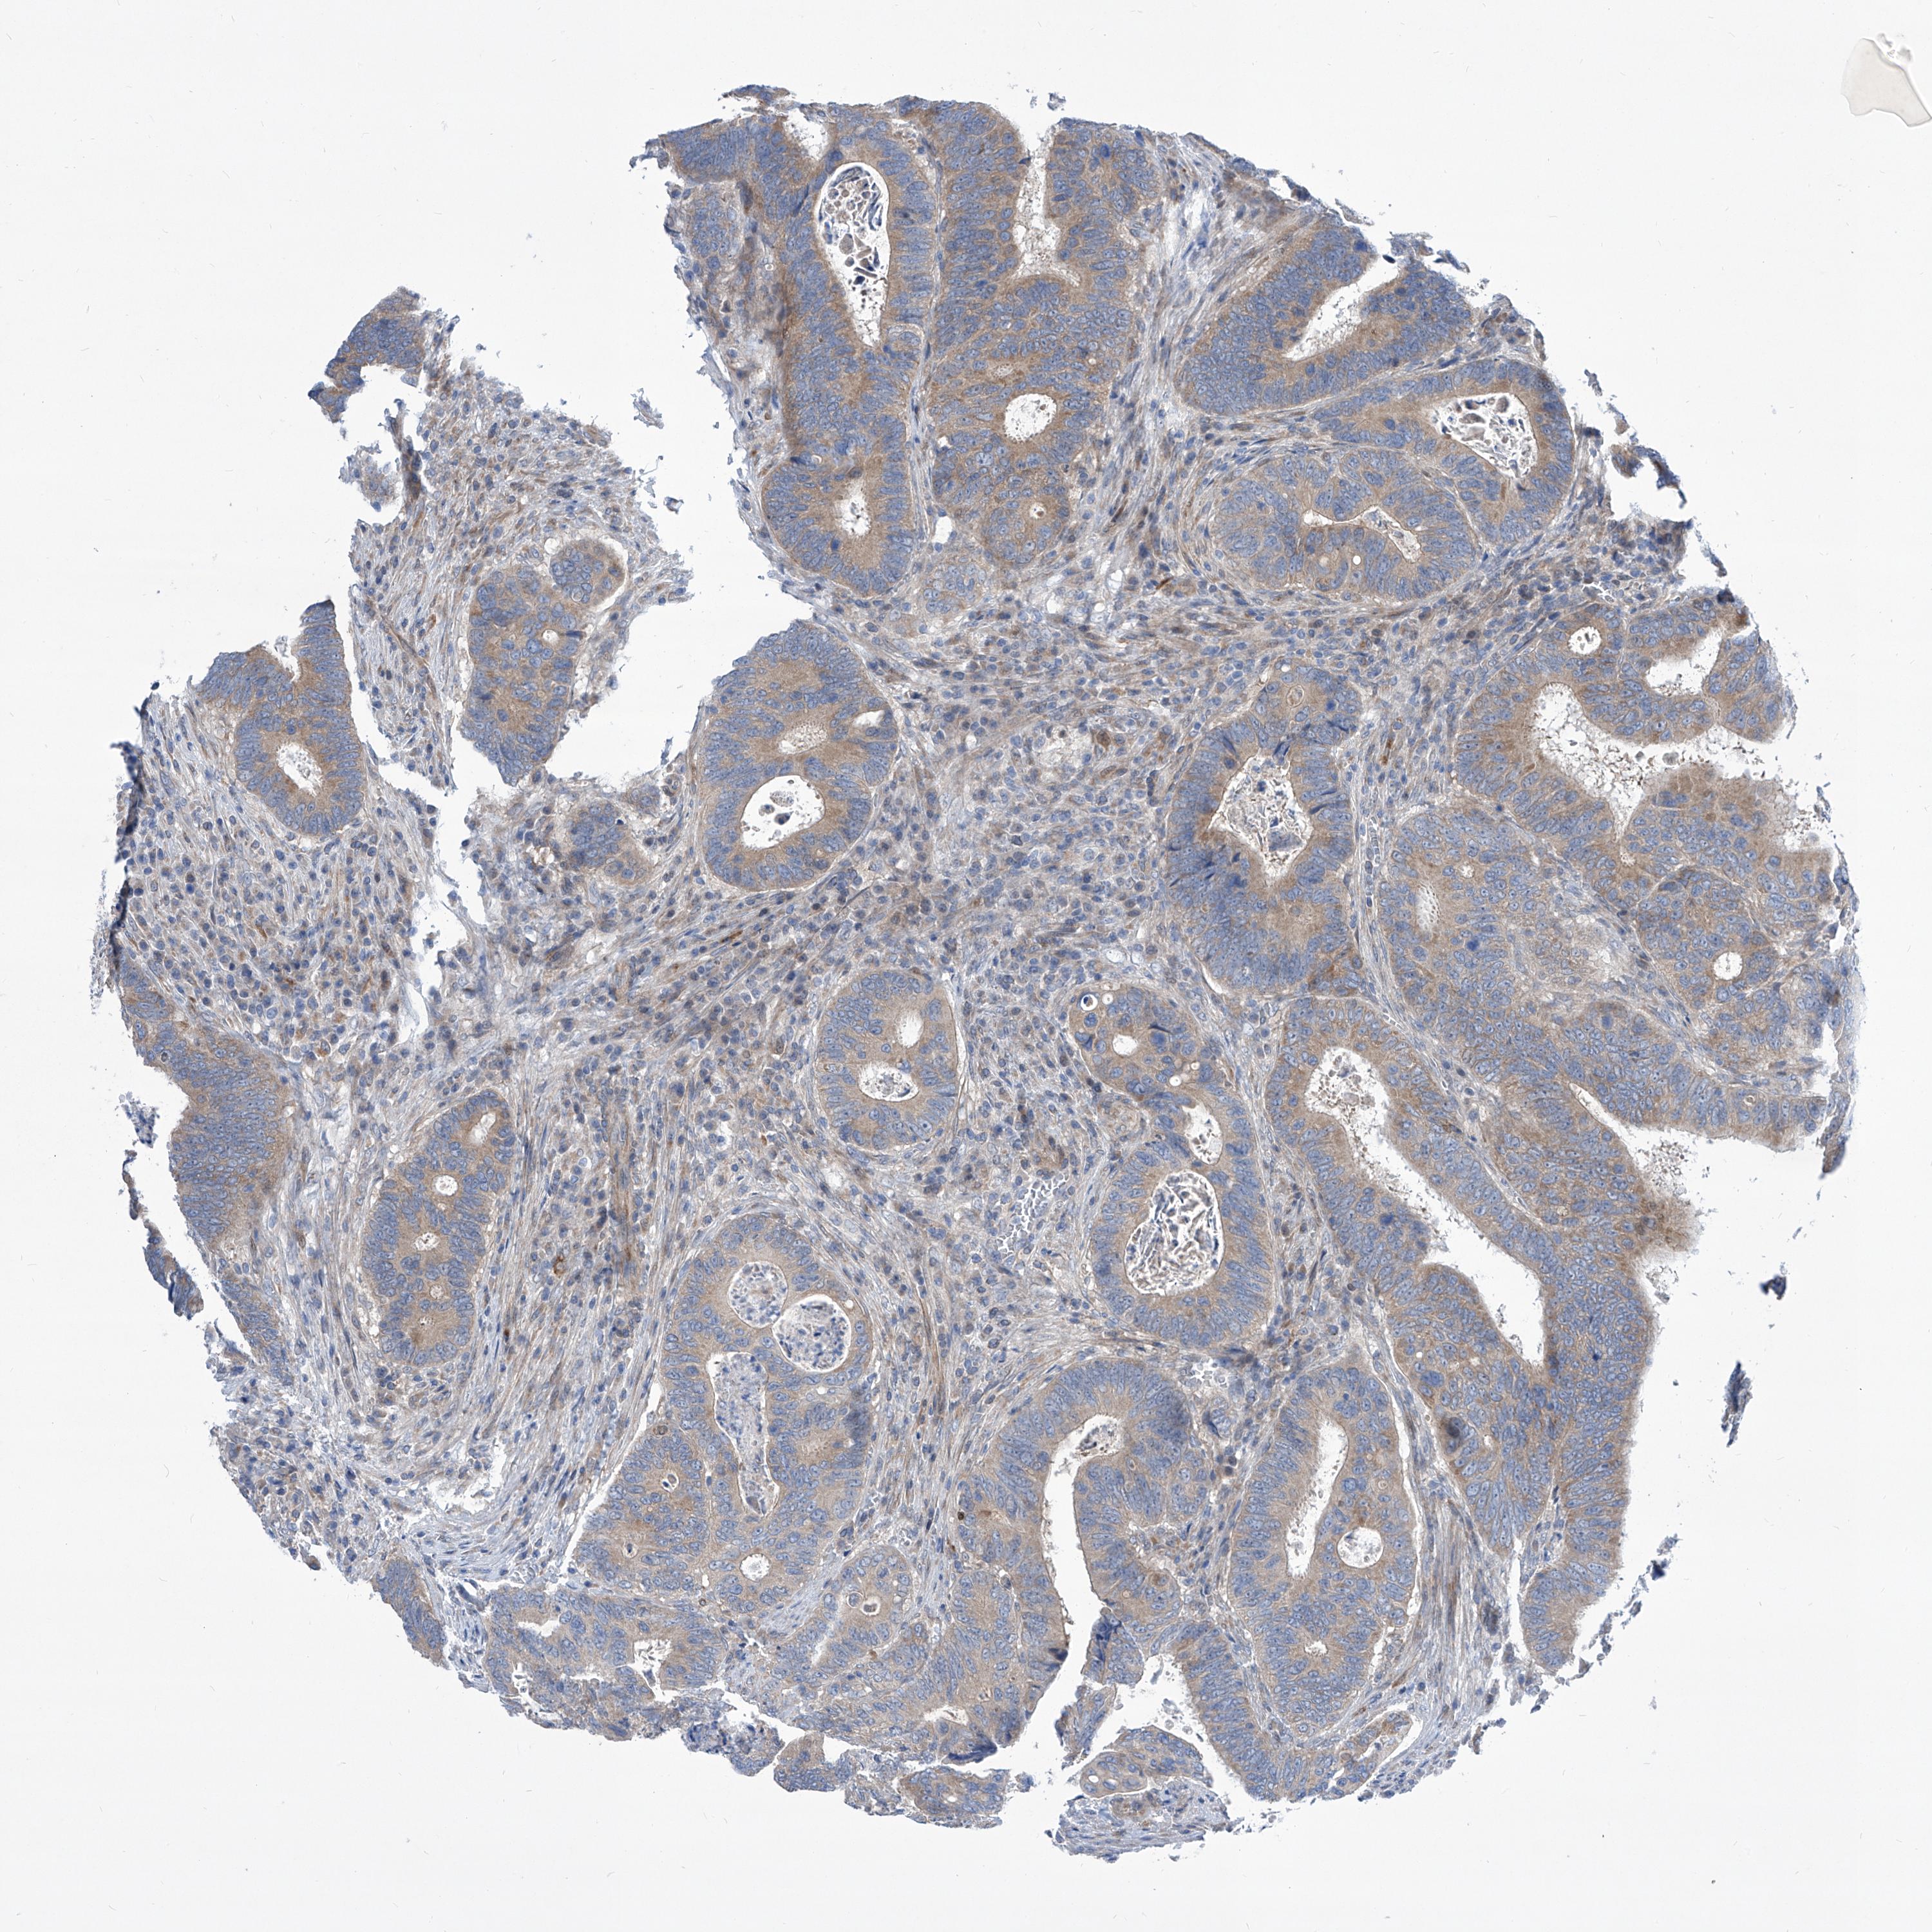

CANCER COLORECTAL CANCER Show tissue menu

Colorectal cancer

Colon adenocarcinoma